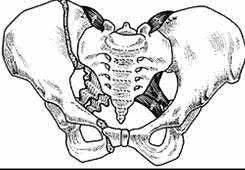

A 20-year-old patient presents after jumping from the window of a burning building with a sacral fracture. Which of the following fracture patterns seen in Figures A through E would give this patient the highest risk of associated nerve injury?

Answering this question relies on knowledge of the Denis classification of sacral fractures and their associated risks of nerve injury. Figure A represents a Denis Zone 3 (medial to the foramina) sacral fracture, which has the highest associated risk of nerve injury.

Denis et al outlined a novel classification system of sacral fractures based on the position of the fracture line relative to the sacral foramina. The authors found a 56.7% incidence of nerve injury in fractures that extended medial to the sacral foramina (zone 3), compared with 28.4% for fractures through the

foramina (zone 2), and 5.9% for fractures lateral to the foramina (zone 1).

Mehta et al reviewed the current principles for management of sacral fractures. They note that bowel, bladder and sexual dysfunction occur in 76% of patients with zone 3 sacral fractures.

Illustration A below demonstrates the Denis classification of sacral fractures. Incorrect Answers: